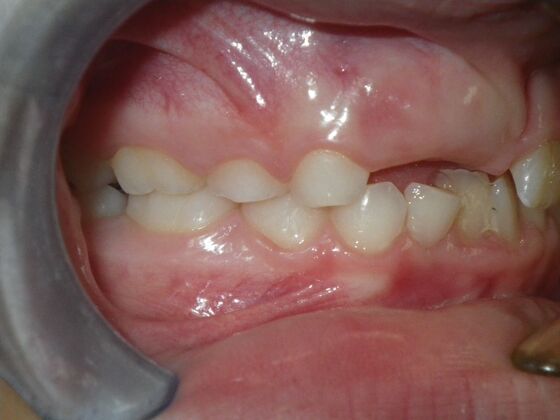

Patient presents with delayed eruption of the upper right central incisor and lower anterior crowding. Treatment plan to include exposure of right central incisor with bracket placement and correction of lower anterior crowding.